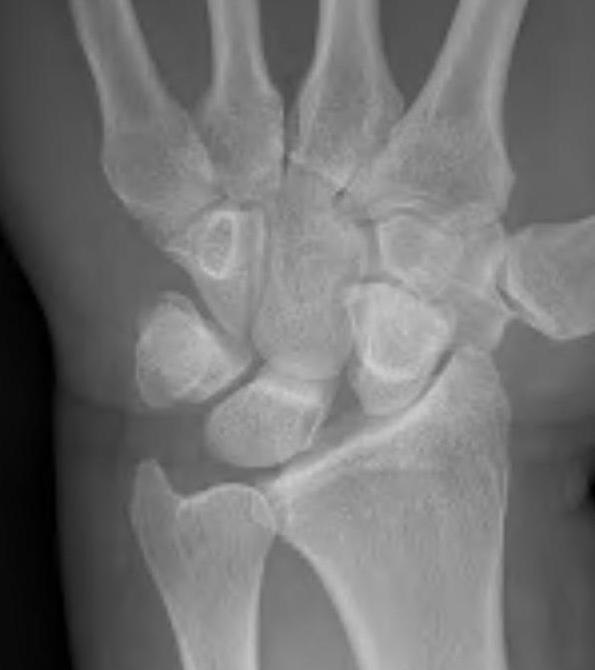

Lateral xray

Increased scapholunate angle > 60o

- scaphoid flexed & lunate extended

- usually 30 - 60o

Scapholunate angle 80o